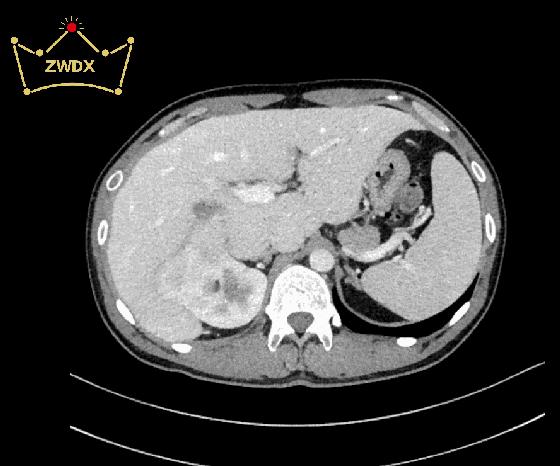

横断面

临床病史: 患者男,35岁,右肾区疼痛三月余,入院检查CT显示,右肾中下极见巨大软组织密度团块影,长度约14.8cm,其内密度不均匀,增强扫描明显强化,与右侧肾盂、肾盏及输尿管移行部分界不清,贴近临近肝脏、下腔静脉。右侧肾盂、肾盏扩张、积水。右肾未见明显异常强化。